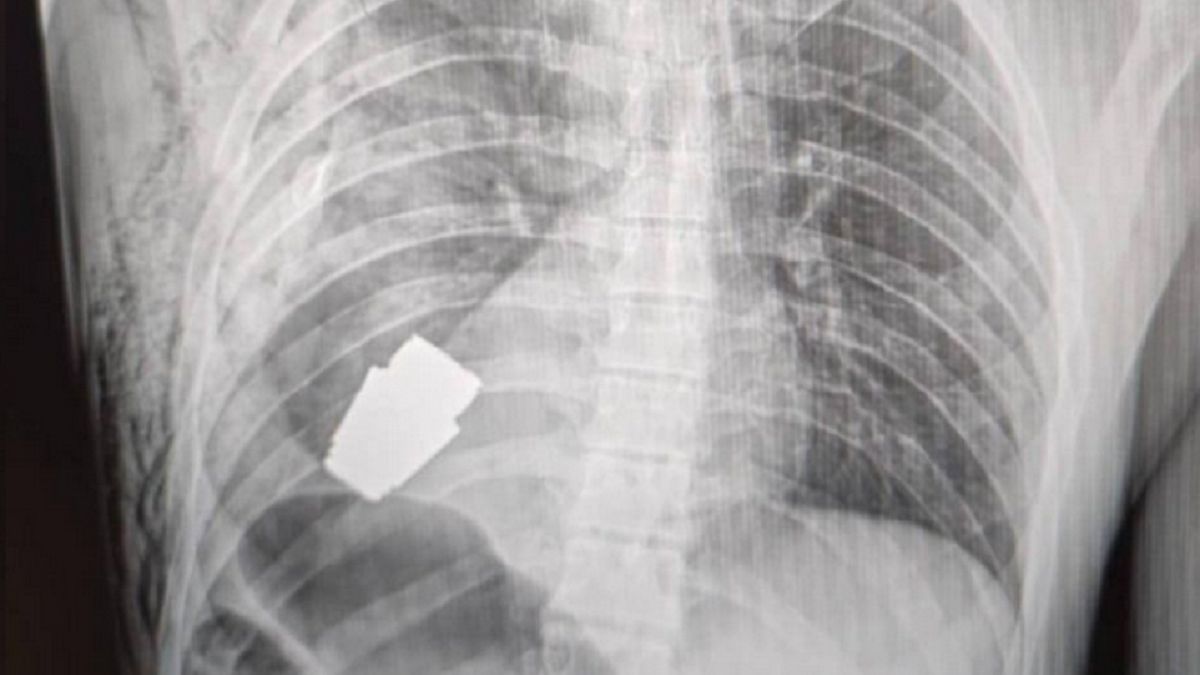

Do jednego ze szpitali wojskowych trafił żołnierz z nietypową dolegliwością. Jak przekazuje portal "Ukraińska prawda" w jego ciele utkwił granat VOG-25, który nie eksplodował.

Niewybuch był śmiertelnym zagrożeniem nie tylko dla samego żołnierza, ale także dla personelu medycznego. Granat mógł w każdej chwili wybuchnąć, dlatego podjęto decyzję o wezwaniu saperów, którzy mieli czuwać nad zabiegiem. Sytuację pogarszał fakt, że granat utknął w niewielkiej odległości od serca poszkodowanego.

VOG-25 to bezłuskowy pocisk odłamkowy kalibru 40 mm. Zasięg pokrycia odłamkami wynosi ok. 70 metrów kwadratowych. Jego mechanizm jest skonstruowany w taki sposób, aby maksymalnie zwiększyć pole rażenia. Po upadku na ziemię następuje detonacja niewielkiego ładunku. Granat unosi się na wysokość kilkudziesięciu centymetrów i dopiero wtedy wybucha właściwy ładunek.

Nie każda rana serca jest śmiertelna! Wojskowi lekarze przeprowadzili operację usunięcia niewybuchu granatu VOG z ciała żołnierza. Został usunięty w obecności dwóch saperów, którzy czuwali nad bezpieczeństwem personelu medycznego. Operację przeprowadził Andrij Werba, jeden z najbardziej doświadczonych chirurgów Sił Zbrojnych Ukrainy, bez żadnej elektrokoagulacji, ponieważ granat mógł wybuchnąć w każdej chwili – zrelacjonowała na Facebooku Hanna Malar, wiceminister obrony Ukrainy.